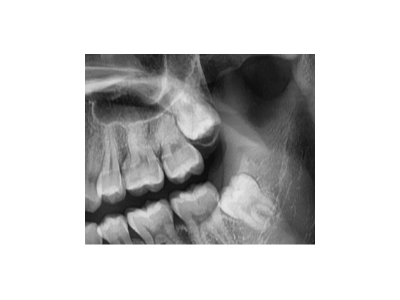

既然「智齒」不宜久留,為什么不能一次性拔掉?

智齒又被稱為第三磨牙,一般有1~4顆不等。由于生長(zhǎng)空間有限,很多智齒無(wú)法正常萌出,它會(huì)歪著長(zhǎng)、橫著長(zhǎng),甚至野蠻生長(zhǎng)……